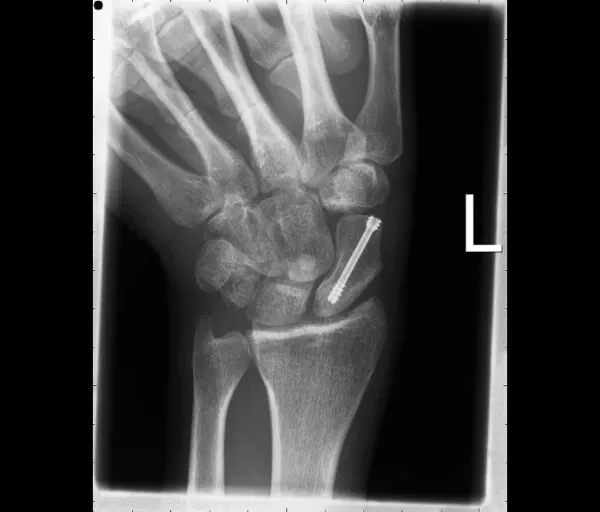

Operatief

Nodig bij:

- Proximale poolfracturen (slechte bloedvoorziening)

- Verplaatste breuken

- Non-union of malunion

Behandelingen:

- Schroeffixatie: vergroot de kans op genezing en verkort de gipsperiode

- Percutane techniek voor recente, niet-verplaatste breuken (klein sneetje)

- Open ingreep voor verplaatste breuken

- Bij non-union/malunion: aanvulling met botgreffe uit het bekken of het spaakbeen